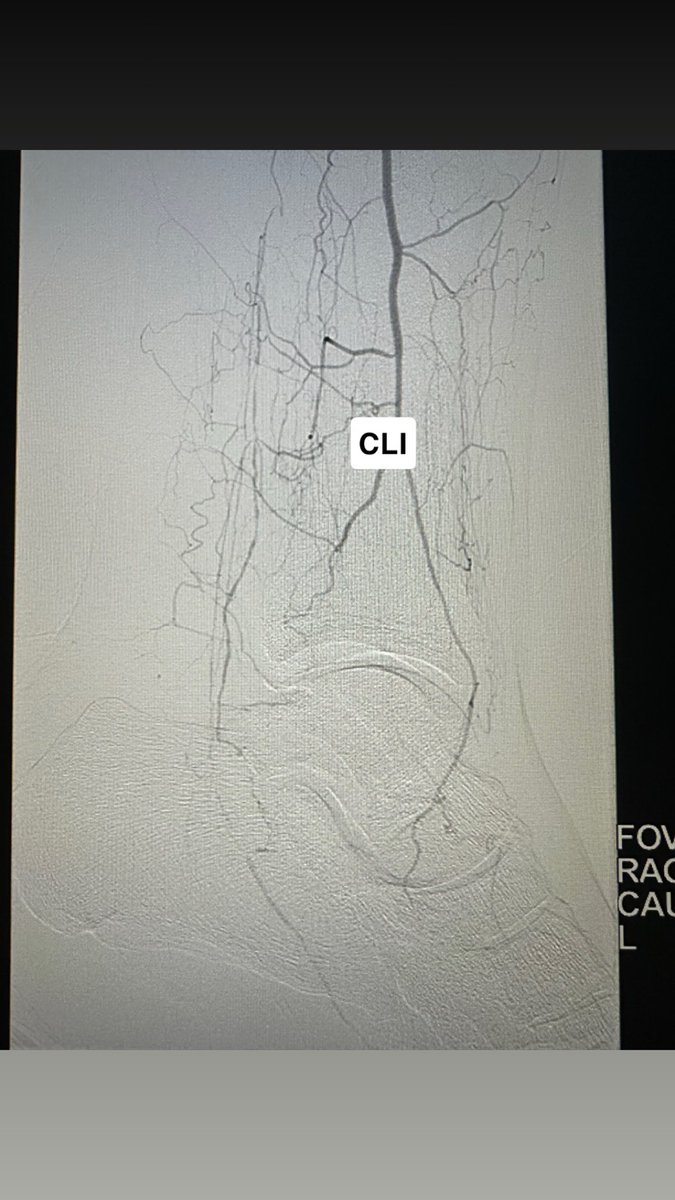

تقنيات #الأشعة_التداخلية ساهمت بفضل الله في إعادة التروية للقدم المصابة بجروح السكري والغرغرينا، مما ساعد بشكل مباشر وغير مباشر في الحفاظ على الأطراف وتقليل الحاجة للبتر، وتحسين جودة الحياة للمريض وعائلته. تُجرى الإجراءات عادةً تحت تخدير موضعي مع إمكانية الخروج في نفس اليوم.

الدكتور حسان المقبل: الآن يوجد علاج للغرغرينه ولله الحمد والا داعي للبتر بإذن الله. #هزة_أرضية #زلزال